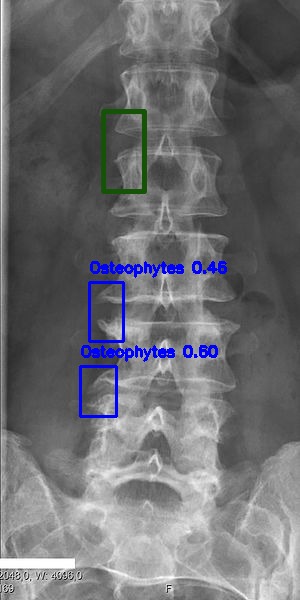

Automated Lesion Detection and Localization: Visual demonstration of the cascaded DERNet-YOLO11 framework on VinDr-SpineXR benchmark images. The figure presents eight representative cases including seven pathological conditions with precise bounding-box localization: (a) Vertebral Collapse, (b) Osteophytes, (c) Spondylolisthesis, (d) Surgical Implants, (e) Disc Space Narrowing, (f) Foraminal Stenosis, (g) Other Lesions, alongside (h) a Normal spine radiograph for comparison. Each pathological case demonstrates the model's capability to accurately detect and spatially localize subtle lesions despite significant class imbalance (46.9:1 ratio), small object scales (often <1% of image area), and anatomical structure overlap. The localization boxes validate the clinical applicability of the integrated triage–localization pipeline.

Osteophytes

(b) Osteophytes